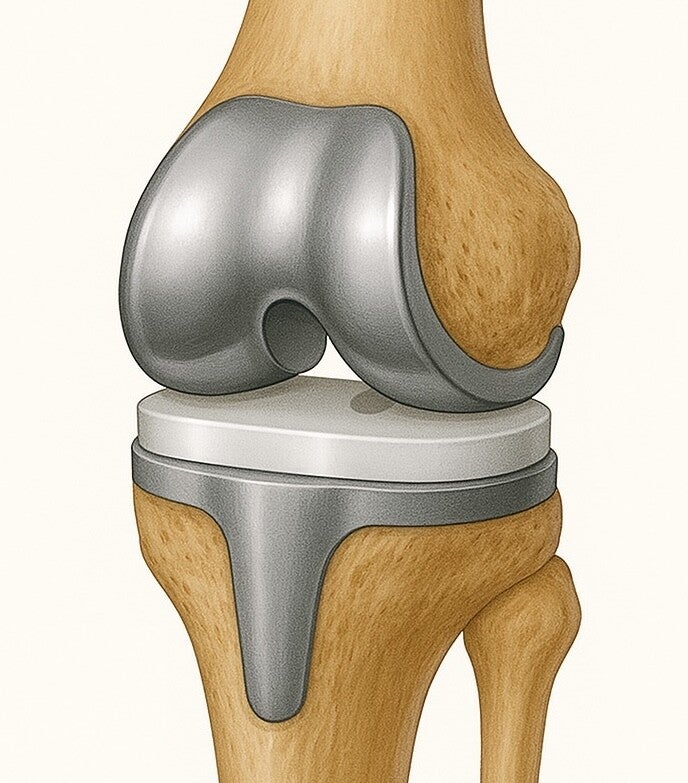

Totale knieprothese

Bij deze operatie worden de versleten uiteinden van het dijbeen en scheenbeen vervangen door metalen prothesedelen, die meestal door middel van botcement stevig verankerd worden. Daartussen komt een kunststof schijfje, dat de spanning tussen de prothesedelen in stand houdt en de wrijving vermindert.